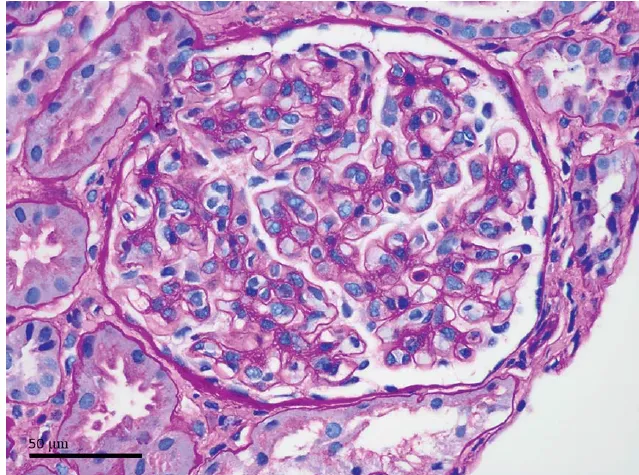

Devido os níveis persistentemente elevados de Cr, mesmo após 3 meses da descontinuação do inibidor de checkpoint, o paciente foi internado para realização de biópsia renal. A avaliação urinária não identificou proteinúria, hematúria e piúria estéril, mas a microglobulina urinária β-2 aumentou para 3667 mg/L. A biópsia renal revelou nefrite tubulointersticial aguda. O tratamento com prednisolona foi iniciado para IRA relacionada ao inibidor de checkpoint, e os níveis de Cr diminuíram progressivamente para 1,53 mg/dl em seis meses.

adversos imunes são conhecidos, sendo a NIA a principal forma quando ocorre acometimento renal. A biópsia renal é essencial para identificar a IRA relacionada ao inibidor de checkpoint e deve ser sempre considerada em pacientes que desenvolvem IRA estágio 2 ou 3, ou IRA estágio 1 persistente ou progressivo.

1. A nefrite tubulointersticial aguda o evento adverso mais comum no rins dos pacientes tratados com inibidores

de checkpoint